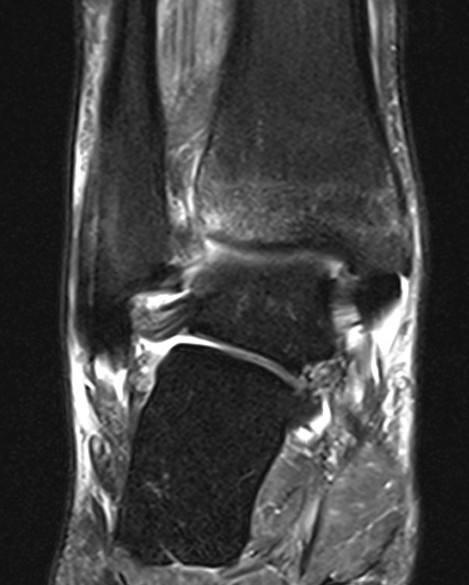

Talus ostechondral lesions

- talar dome and tibial plafond for chondral lesions

Posterior talus osteochondral lesions